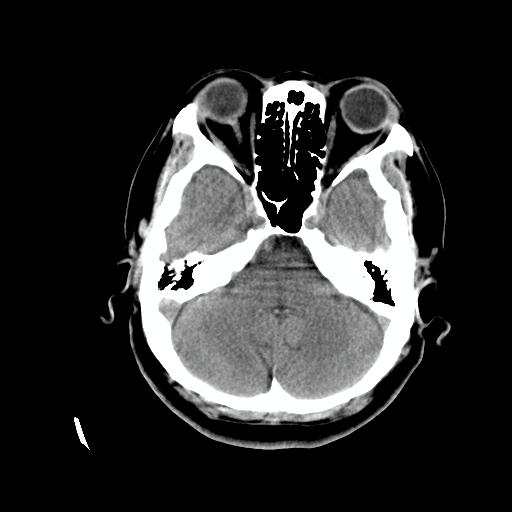

标题: CT24768:双侧脑室内囊性病变,主各位站友会诊。 [打印本页]

标题: CT24768:双侧脑室内囊性病变,主各位站友会诊。

患者女,62岁,临床提供头痛、头晕数月,无恶心及呕吐,近日加重。请各位站友看看,能否定为双侧脑室脉络丛囊肿,如果不能,应考虑什么?谢谢!

室管膜钙化 脑内多发钙化灶 可考虑寄生虫 结核等颅内感染

首选考虑---脑囊虫病。